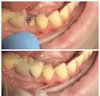

Терапия:

-Консультации

-Художественные реставрации.

-Лечение к\к вертикальная конденсация гуттаперчей.

-Лечение слизистой оболочки полости рта.

Ортопедия :

-Протезирование при частичной потере зубов

Протезирование при полной потере зубов.

-Штампованные коронки.

-металлопластмассовые коронки

-Микропротез (бабочка)

Хирургия:

-Удаление 1-корневых, 2 корневых зубов.

-Рассечение уздечки языка.